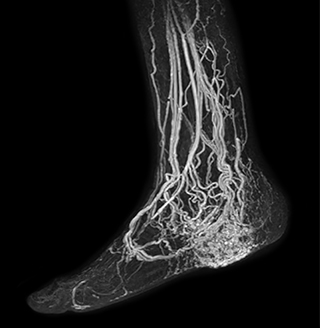

The subtractionless peripheral MR angiography shows improved vessel-to-background contrast and high resolution. Ingenia Ambition 1.5T.

Another example is the foot examination for diabetic patients, which has improved dramatically. “The forefoot is generally difficult to image with MRI because of the inhomogeneities that the toes create – it’s hard to obtain good fat saturation in that area. Here, mDIXON made a huge difference right away, we obtain much better image quality,” Dr. Peña says. “Using mDIXON, Compressed SENSE and the dS FootAnkle coil, we have been able to reduce the scan time, so that we can now also include an additional 3D STIR sequence to visualize both arteries and veins in the foot.”

Avila adds: “In addition, since most of these patients are in a significant amount of pain, it’s important to perform the examination as quickly as possible. With Compressed SENSE and mDIXON we have been able to reduce the scan time from about 45 minutes to just 15 minutes. Not only does this improve patient comfort, we see that it also helps us acquire images without motion artifacts, which is critical to making a confident diagnosis.”